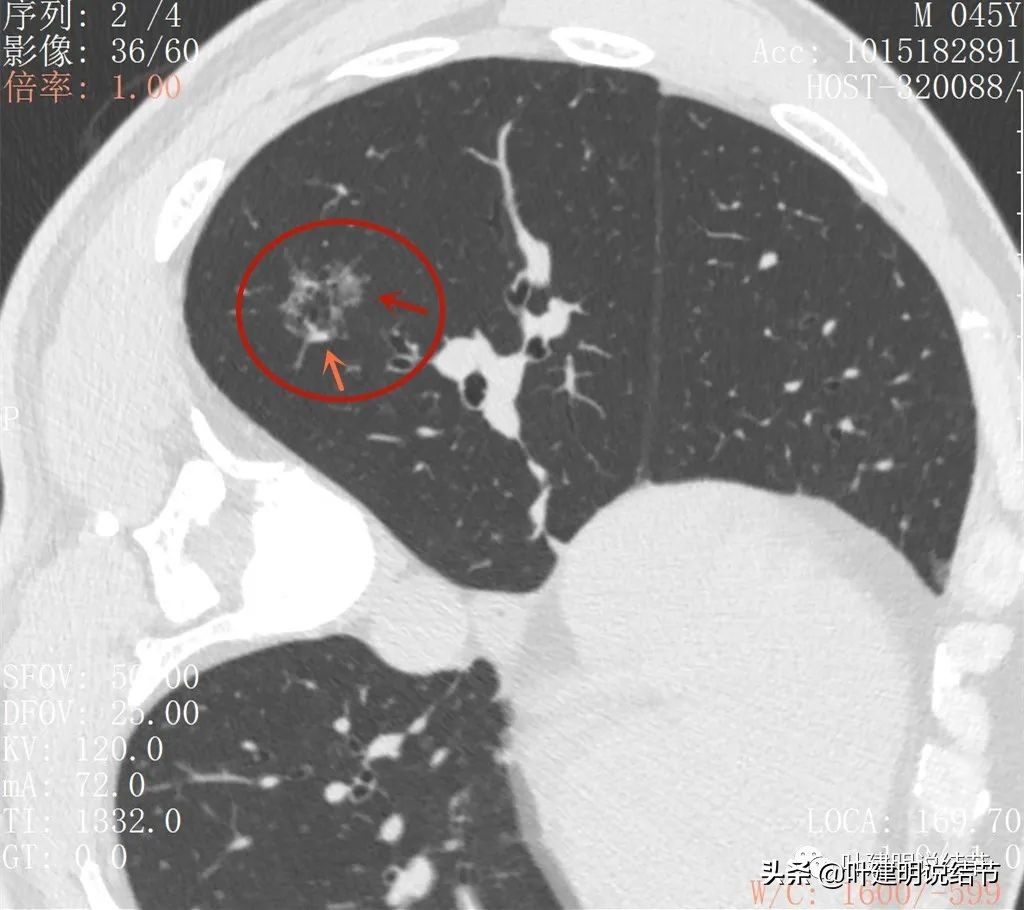

后处理影像:

病灶不规则形,中间多空泡状结构,轮廓较清

似有棘突或少许毛刺样(紫色箭头),边缘血管异常增粗(桔色箭头)

病灶有偏实性成分(粉色箭头),有扩张的细支气管(黄色箭头),轮廓较清(红色箭头),有血管穿行与血管进入(桔色箭头)

病灶有血管进入(桔色箭头),有分叶(砖色箭头),整体轮廓清(红色箭头),支气管扩张明显(黄色箭头)

血管征明显,从不同角度与方向进入,并在病灶内增粗

扩张的细支气管较为僵硬,病灶整体轮廓清,磨玻璃成分明显

病灶内部血管联通以及偏高密度成分,血管进入并分支

上图这个层面非常不舒服:病灶多处血管进入,并图像下方这个区域是较粗血管穿过病灶区域,而且有血管被病灶侵蚀的感觉,分支发出进入病灶后也未见穿出;管壁也不平整;病灶整体轮廓很清楚,瘤肺边界也清;病灶内部密度不均杂乱;有分叶与毛刺样征。感觉是较为典型的恶性影像。

上图也是多处血管进入,整体轮廓清,内部密度不均。唯一不是很符合恶性的是病灶密度不够密实,显得有点散

到这个层面是更为典型的恶性影像特征:病灶表面分叶不平整(砖色箭头);多支血管进入(桔色箭头);病灶轮廓很清(红色箭头)。而且磨玻璃成分明显,密度杂乱不均,内部有偏实性密度。